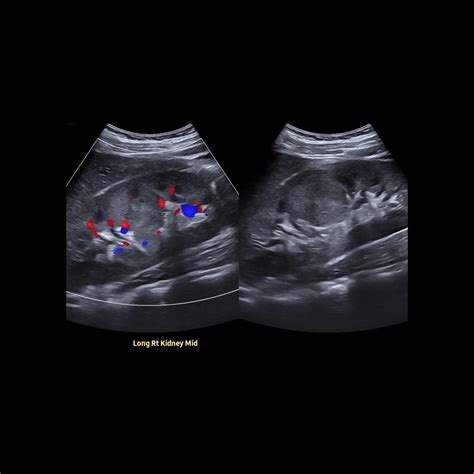

• hypertrophied column of bertin radiology

• prominent column of bertin kidney

• hypertrophied column of bertin

• column of bertin hypertrophy

• column of bertin kidney